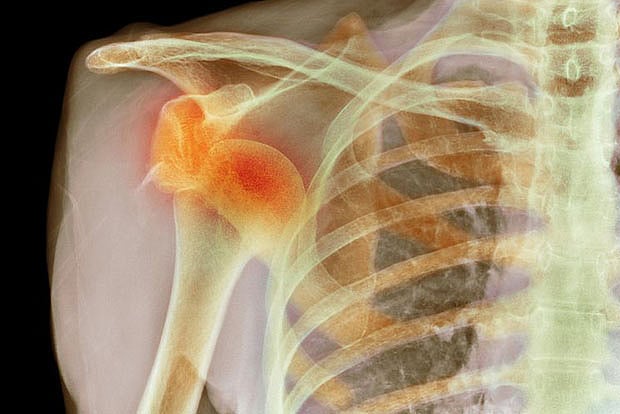

Shoulder dislocation usually occurs when the ligaments, tendons and muscles around the joint get stretched, torn or loose thereby, failing to keep the upper arm bone joint in the shoulder socket.

When the joint repeatedly slips out of place it leads to chronic shoulder instability. Reasons for the condition can vary from severe injury, fall or trauma, overuse of the joint to genetic disorders that cause joint loosening. Although more common amongst sports persons, the condition can affect anyone whose shoulder dislocation is not treated properly.

In severe cases, it can also result in visible deformity leading to a compromised quality of life. Therefore, it is important to consult an orthopedist who can help with accurate diagnosis through physical examination of the shoulder joint and an X-ray or MRI.